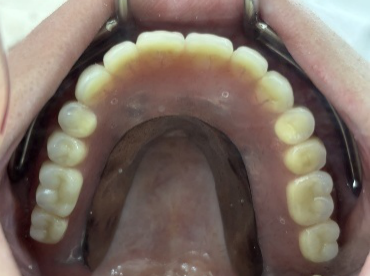

After

【義歯を装着したところ】

【義歯を外したところ】

【マグネット式総入れ歯】

上顎

下顎